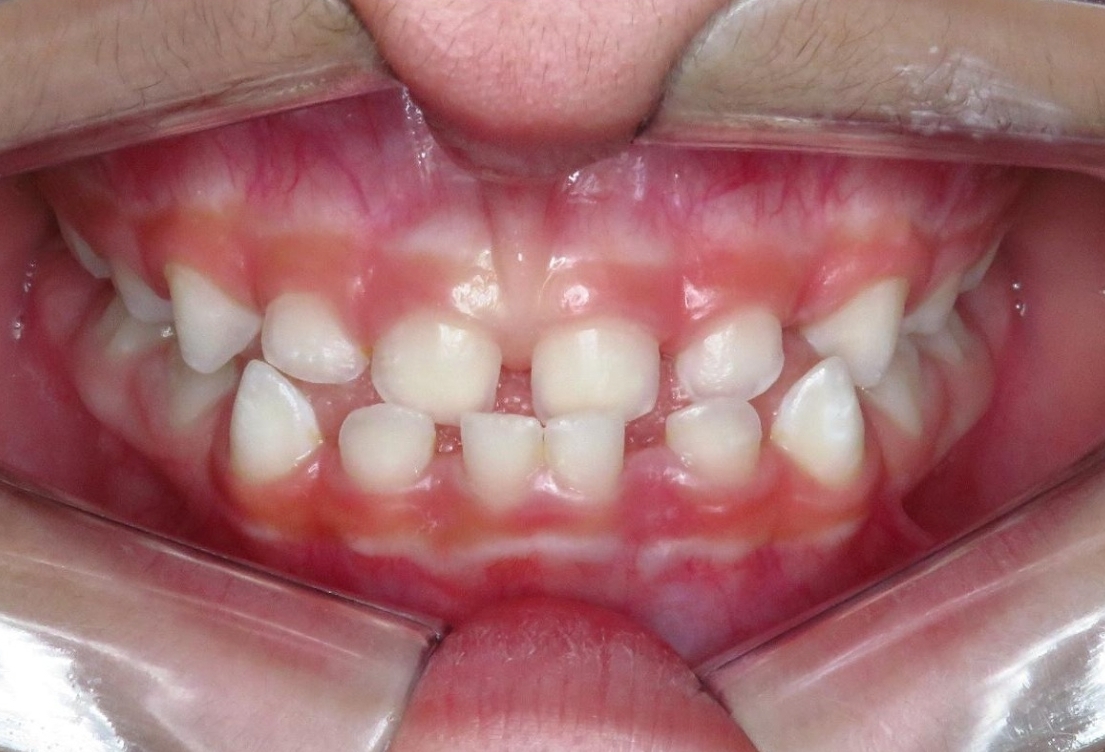

R.P.B.

ORTODONTIA MIOFUNCIONAL